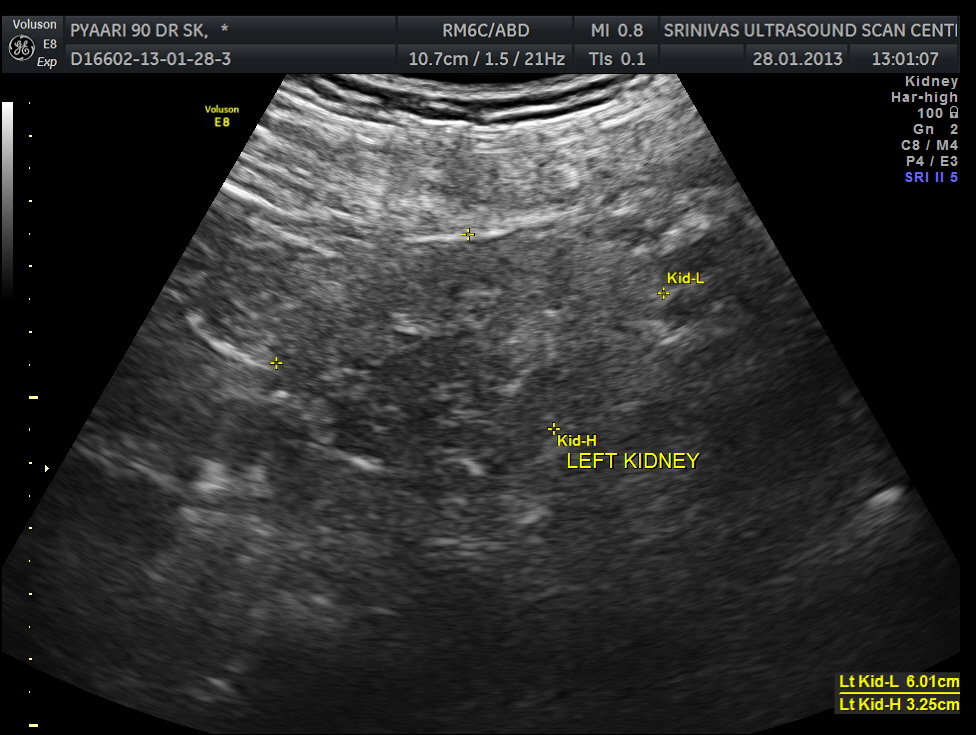

Both kidneys show features of medical renal disease.